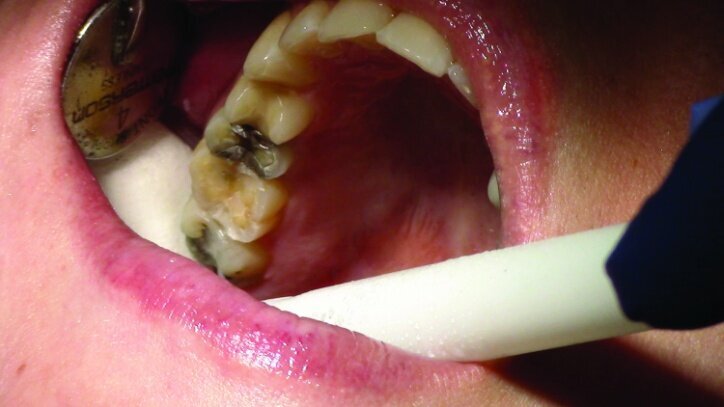

This patient presented for restorations of teeth #3 and #4 (Fig. 1a). Because of the size of the existing restorations, these teeth were diagnosed as structurally compromised (Figs. 1b, c). The prognosis without treatment was fair.

The restorations were to be completed with PlanScan chairside CAD/CAM technology in the same visit.